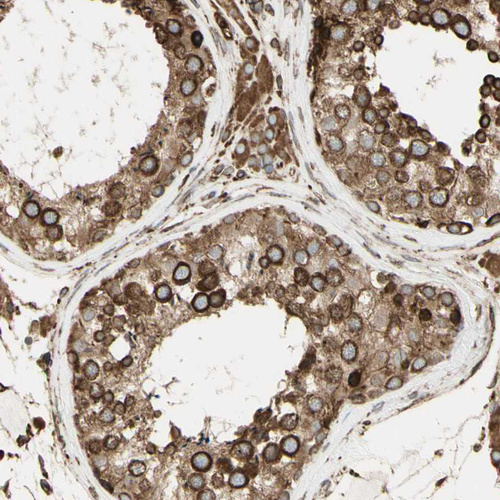

Immunohistochemical staining of human cerebral cortex, placenta, testis and tonsil using Anti-CANX antibody HPA009696 (A) shows similar protein distribution across tissues to independent antibody HPA009433 (B).